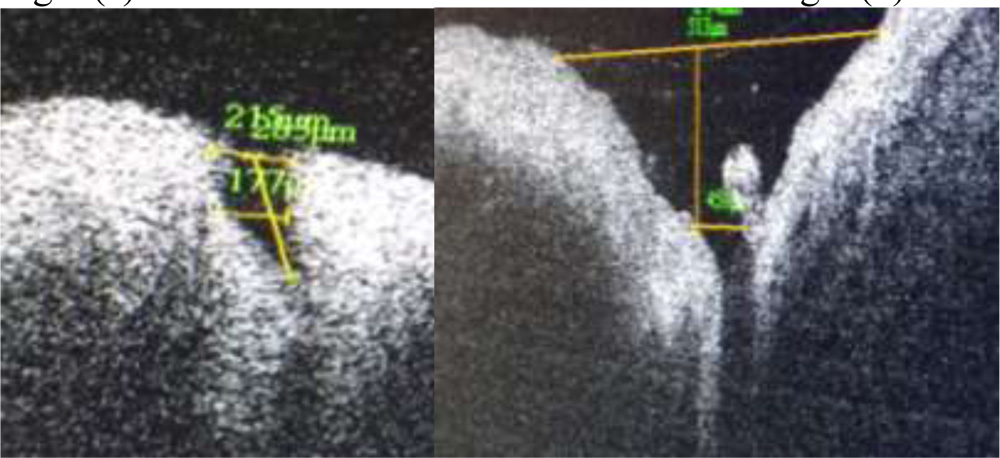

Punctalshape , contents, angulation of the medial and lateral wall was noted.Measurement of outer and inner punctal diameter and depth was done using adjustable distance measurement tool. A tangent drawn over the punctal opening towards lid margin was used to measure outer punctal diameter. Inner punctal diameter was measured with the help of a line drawn above the abrupt narrowing of inner lumen. A perpendicular was drawn from outer punctal diameter towards the base till the inner punctal diameter to measure the depth of the punctum.(Fig 2)

Fig 3 (e) Fig 3 (f)

Fig 3(a-f) Range of punctal morphological variation of shapes detected on SDOCT

This study recorded a mean outer punctal diameter of 700.1± 424.09 µ with a wide range of variation. The median value for outer punctal diameter was 584.5µ. This is more than previously recorded values of 214.7µ by Wawrwyznskyet al (2014), 247µ by Allam and Ahmad (2015) and 400.16 µ by Kamal et al7(2015). Timlinet al8recorded a mean outer punctal diameter of 646± 150 µ. All these values reflect a wide range of variation of punctal morphology, particularly punctal shape and depth. A saucer shaped punctum was found have a larger extent compared to a narrow v shaped punctum. A cross line method of scanning was used by Allam and Ahmed while linear scanning was done by Timlinet al and Kamal et al.

Mean inner punctal diameter was recorded as 245.5± 127.54µ at the level of narrowing and change in curvature of inner walls to a vertical from a horizontal one. A definite junction between lower end of punctum and vertical canaliculus could be identified as inner punctum. Inner punctal diameters were found to range from 101µ to 479µ. Allam and Ahmad recorded a mean inner punctal diameter to be 234± 139µ at a similar level. Timlinet al recorded a value of 50 ± 104µ at a depth of 500 µ from external punctum while inner punctal size was recorded as 125± 61µ mid way between punctum and visible lower end by Kamal et al.

The present study recorded mean punctual depth as 390.85± 229µ with a range of 132µ to 866µ. This is comparable to the mean punctal depth recorded by Allam and Ahmad et al as 252 ± 127µ In contrast Timlinet al recorded this value as 544± 327µ . Kamal et al recorded a depth of 890± 155µ. These two measurements represent the vertical canalicular depth as there is no identification of a separate inner punctum in all cases. Wawrzynskietal reported a mean depth of 753 ± 216 µ. This depth is representative of punctal and vertical canalicular depth. All studies report a depth of less than 2mm on imaging. It is difficult to identify the end point of vertical canaliculus and beginning of horizontal canaliculus by OCT imaging. Proximal lacrimal system has been easier to image and three dimensional reconstruction has been shown to be possible by Kamal et al.